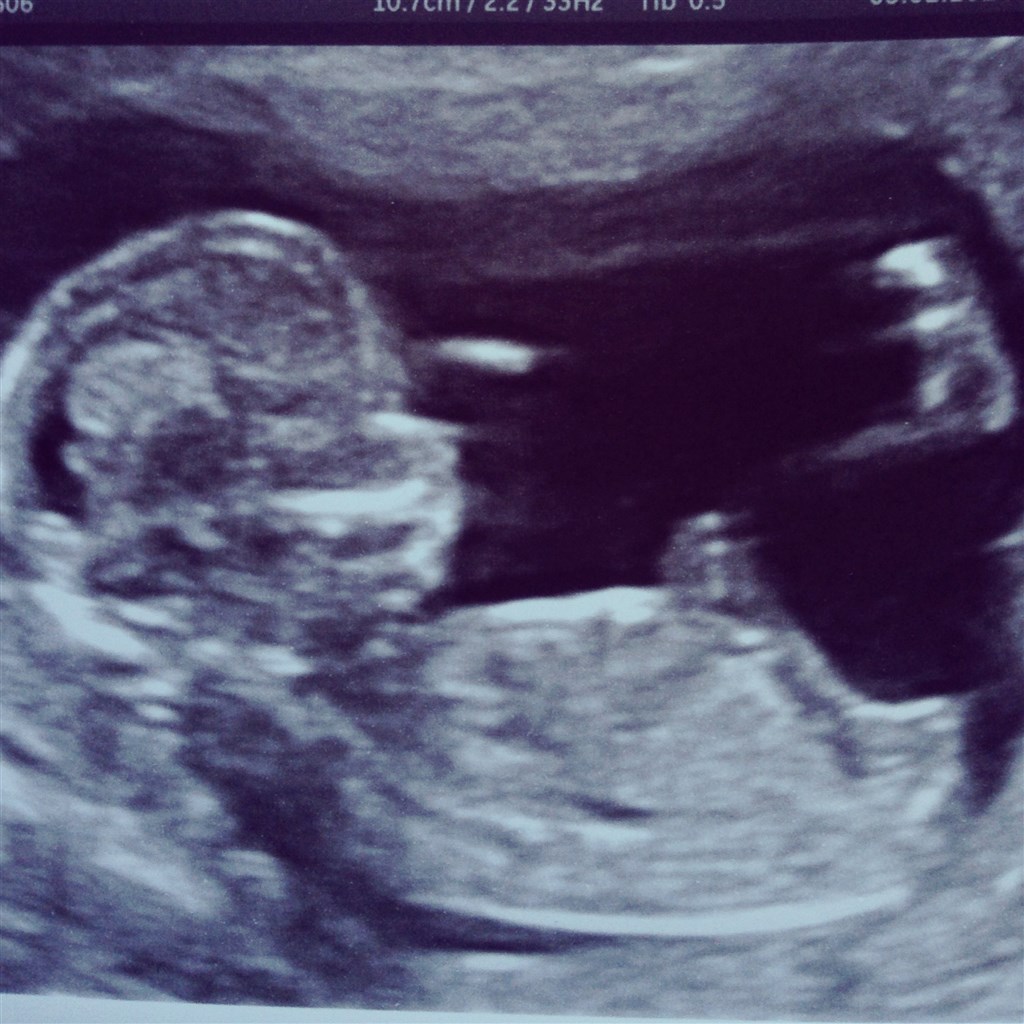

Babyen er 13+4 og har termin 9 august. Kunde se en lille tap men jm ville ikke udtale sig om køn fordi de ligner hinanden nu.

Så at fingrene var på plads og hjertelyden var fin ca 160 i minut

En stille og rolig baby inde i maven som laver små bevægelser. Glæder mig til at få køn at vide.